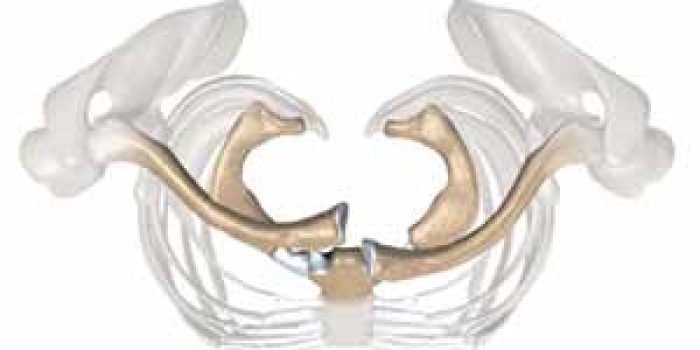

استخوان ترقوه یا کلاویکل در دو انتهای خود با دو استخوان دیگر مفصل میشود. در قسمت داخلی، استخوان ترقوه با استخوان جناغ مفصل شده و در طرف لترال یا خارجی، ترقوه با استخوان کتف یا اسکاپولا Scapula مفصل میشود. مفصل بین استخوان جناغ (یا استرنوم Sternum) و کلاویکل را مفصل استرنوکلاویکولر Sternoclavicular joint مینامند.

در حالتهایی که سر استخوان ترقوه به سمت جلو جابجا شده است، جااندازی با فشار دادن آن به سمت عقب انجام میشود. پس از جااندازی، دست بیمار به مدت دو هفته به گردن آویزان میشود و سپس بیمار تمرینات فیزیوتراپی برای حرکات شانه را انجام میدهد. در مواردی که سر استخوان ترقوه به عقب جابجا شده است، جراح ارتوپدی سر استخوان را با استفاده از گیرههای مخصوصی در دست بگیرد و به سمت جلو برگردانده تا جابجایی را برطرف کند.

گاهی اوقات بیمار دچار دررفتگی مکرر این مفصل میشود. در این موارد هر وقت بیمار شانه اش را به سمت عقب میبرد سر استخوان ترقوه در مفصل استرنوکلاویکولر همراه با یک صدای تقه به سمت جلو میرود و وقتی بیمار شانه را به جلو میاورد مفصل دوباره جا میفتد. در اکثر موارد این عارضه مشکل جدی برای بیمار ایجاد نکرده و نیاز به درمان ندارد. در مواردی که این مشکل برای بیمار آزار دهنده است عمل جراحی انجام میشود که بصورت بازسازی یک لیگامان جدید در محل مفصل با استفاده از تاندون عضله سابکلاویوس Subclavius tendon و یا قسمتی از فاشیا لاتا Fascia lata است.